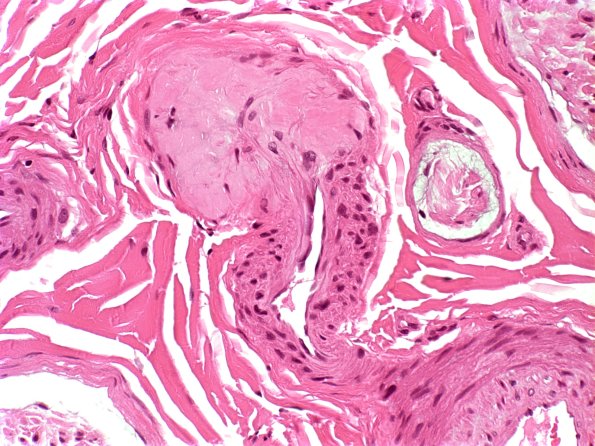

Washington University Experience | PERIPHERAL NEUROPATHY | 14 AMYLOID NEUROPATHY | 22A1 Amyloid neuropathy (Case 22) H&E 1

Deposition of amorphous lightly eosinophilic materials consistent with amyloid is immediately adjacent to an apparently intact arteriolar vessel. (H&E)